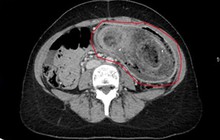

X-quang phổi của người đàn ông (Ảnh: AsiaWire).

Ban đầu, các bác sĩ tại Bệnh viện 909 của Chương Châu nghi ngờ rằng anh Bành, 37 tuổi, bị viêm phổi. Nhưng khi các triệu chứng của anh ta kéo dài, các bác sĩ đã hỏi lại và cuối cùng anh ta thừa nhận rằng anh ta nghiện ngửi mùi tất mà mình đã mang trong suốt cả ngày. Sau khi chụp X-quang, các bác sĩ phát hiện ra anh ta bị nhiễm trùng phổi do nhiễm nấm nghiêm trọng, chính thức được gọi là bệnh nấm phổi (hay Aspergillosis), và nguyên nhân là từ việc ngửi chính đôi tất của mình vào mỗi cuối ngày.

Sau khi chụp X-quang, các bác sĩ phát hiện ra anh ta bị nhiễm trùng phổi do nhiễm nấm nghiêm trọng.